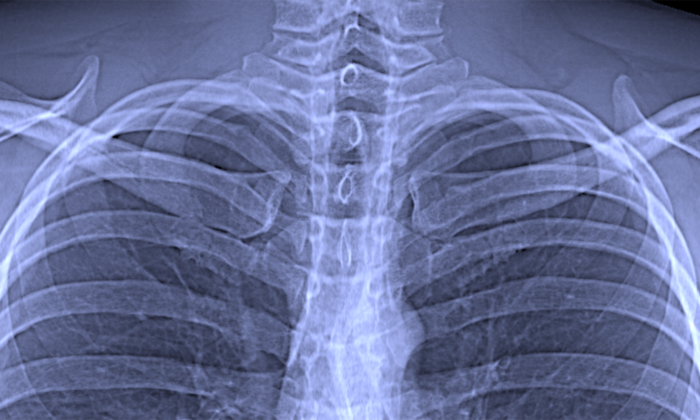

Forschende der Technischen Universität München (TUM) haben ein neues Röntgenverfahren für die Lungendiagnostik erstmalig erfolgreich bei Patienten eingesetzt. Dunkelfeld-Röntgen macht frühe Veränderungen in der Alveolarstruktur infolge der Lungenkrankheit COPD sichtbar, benötigt dafür jedoch nur ein Fünfzigstel der in der Computertomographie üblichen Strahlendosis. Dies erlaubt eine breite medizinische Anwendung in der Früherkennung und dem Therapieverlauf von Lungenerkrankungen.

In normalen Röntgenaufnahmen sind die feinen Unterschiede im Gewebe jedoch kaum sichtbar. Detaillierte diagnostische Informationen liefern erst fortschrittliche medizinische Bildgebungstechnologien, bei denen im Computer viele Einzelbilder zusammengesetzt werden. Eine schnelle und kostengünstige Option mit geringer Strahlenbelastung für Früherkennung und Nachuntersuchungen fehlt bisher.

Die konventionelle Röntgen-Bildgebung beruht auf der Abschwächung des Röntgenlichts auf seinem Weg durch das Gewebe. Die Dunkelfeld-Technologie dagegen nutzt Anteile des Röntgenlichts, die gestreut werden und beim konventionellen Röntgen unbeachtet bleiben.

Die neue Methode nutzt damit das physikalische Phänomen der Streuung auf ähnliche Weise wie die schon länger bekannte Dunkelfeldmikroskopie mit sichtbarem Licht: Diese macht es möglich, Strukturen weitgehend transparenter Objekte sichtbar zu machen. Im Mikroskop erscheinen sie als helle Strukturen vor einem dunklen Hintergrund, was der Methode ihren Namen verleiht.

„An Grenzflächen zwischen Luft und Gewebe ist diese Streuung beispielsweise besonders stark“, erklärt Pfeiffer. „Dadurch lassen sich in einem Dunkelfeldbild der Lunge Bereiche mit intakten, also luftgefüllten, Lungenbläschen klar von Regionen unterscheiden, in denen weniger intakte Lungenbläschen vorhanden sind.“